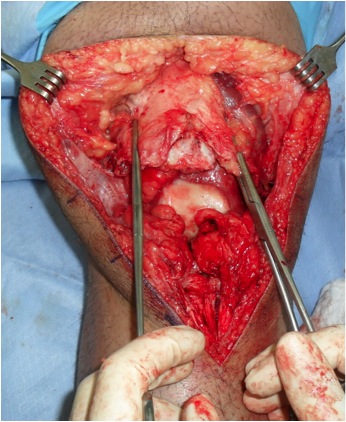

1. Tendon torn off patella

Multiple Bunnell / Krackow Sutures to Patella Tendon

- 2 non absorbable

- drill holes through patella ( 3 - 4)

- pass sutures and tie

- can augment with box fibrewire

Can reinforce with box wire loop

- large gauge wire 18G

- drill hole in tibial tuberosity

- transverse drill hole in patella

- pass in square and tie

- protects patella tendon

- problem is will break / irritate / need removal

- only do if concerned re repair